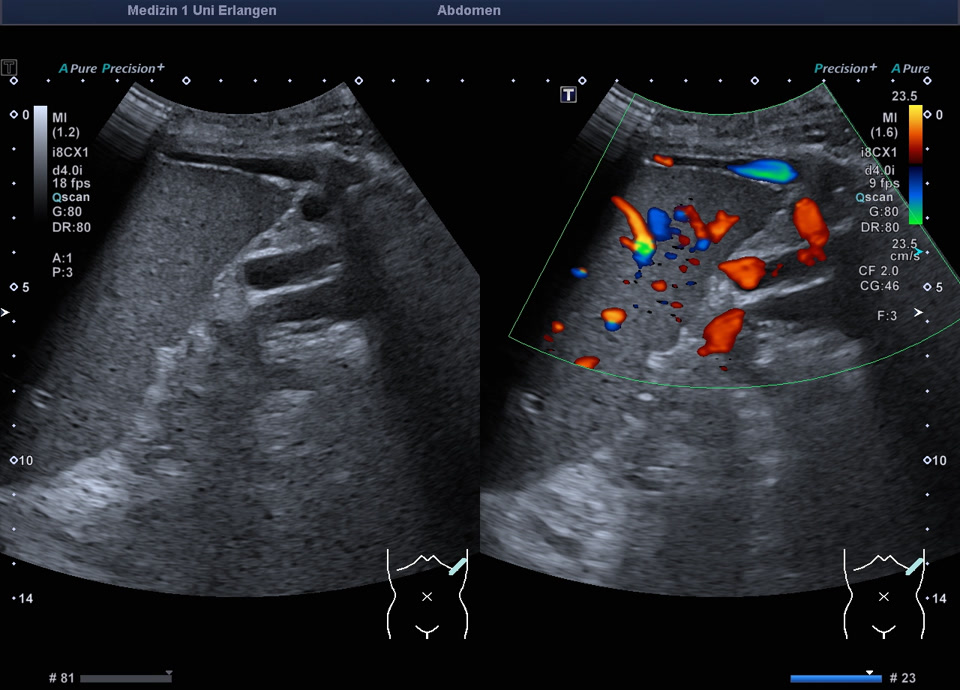

Splenorenale Shunts